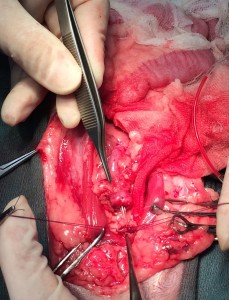

摘出した結石

子宮蓄膿症

子宮内に膿みが貯まり大きくなっています